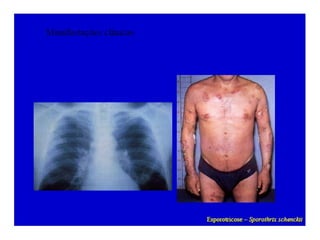

3. Esporotricose:

Geralmente ocorre após a inoculação

acidental na pele e se caracteriza pela formação

de um nódulo ulcerado no local inoculado,

linfangite nodular crônica e linfadenite regional

3. Esporotricose: Geralmente ocorre após a inoculação acidental na pele e se caracteriza pela formação de um nódulo ulcerado no local inoculado, linfangite nodular crônica e linfadenite regional